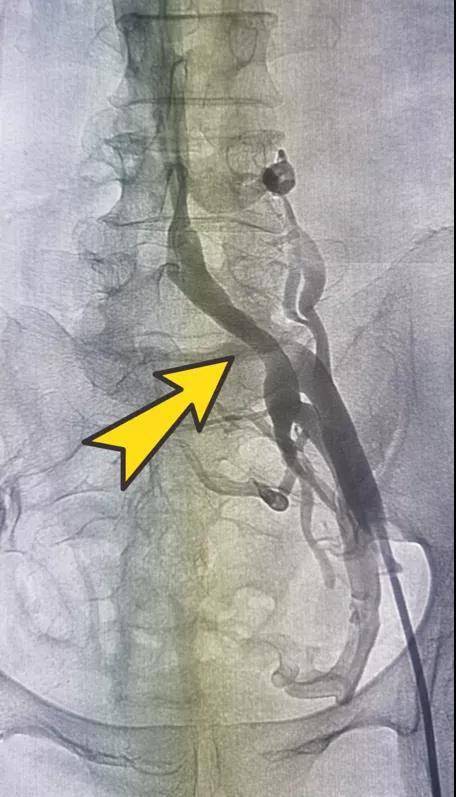

静脉造影图像 。

对罗女士行下肢静脉造影检查 , 发现其左侧髂总静脉明显狭窄 , 子宫附件静脉丛、腰静脉和骶前静脉丛显影明显 。

真相终于浮出水面 , 一直以来困扰罗女士的腿肿 , 缘是左侧髂总静脉受压出现血管狭窄所致 。 只有当血管狭窄的问题得以解除 , 方能从根本上改善腿肿症状 。